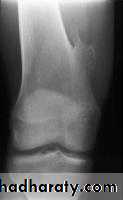

Rx : curettage + bone graftOsteoid osteoma

Patient < 30 yrPain > at night relieved by aspirin

XR : radioluscent nidus surrounded bysclerosis

Any bone except the skull